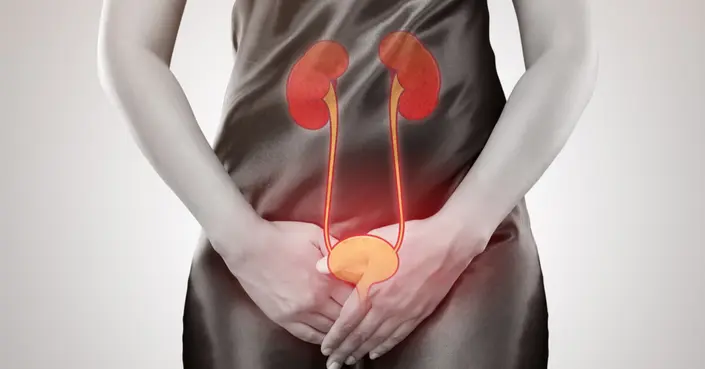

الشعور بالألم أو الحرقة أثناء التبول، المعروف طبيًا باسم عسر البول، تجربة مزعجة وشائعة قد تصيب الكثيرين في مرحلة ما من حياتهم. بينما قد يكون عابرًا في بعض الأحيان، فإن تكرار هذه الحالة يشير غالبًا إلى وجود مشكلة صحية كامنة تتطلب اهتمامًا وعلاجًا.

في هذا الدليل، نستعرض كل ما تحتاج معرفته عن صعوبة التبول، من تعريفها وأسبابها المتعددة، إلى كيفية تشخيصها وخيارات العلاج المتاحة، بالإضافة إلى نصائح وقائية لتعزيز صحة المسالك البولية.

ما هي صعوبة التبول (عسر البول)؟

صعوبة التبول، أو ما يُعرف طبيًا بعسر البول (Dysuria)، هو مصطلح يصف الألم، الحرقة، أو الانزعاج الذي يشعر به الشخص أثناء عملية التبول. هذا الإحساس قد يكون خفيفًا أو حادًا، وقد يحدث في بداية التبول أو في نهايته.

تُعد هذه المشكلة أكثر شيوعًا بين النساء، ولكنها قد تصيب الرجال أيضًا، وخاصة مع التقدم في العمر. فهم ما يشير إليه جسمك هو الخطوة الأولى نحو معالجة السبب الكامن.